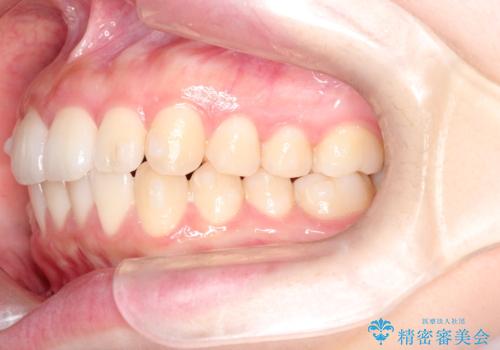

前歯のがたつきをインビザラインで目立たない矯正

- 上下の前歯のがたつきを主訴に来院されました。

マウスピースでの矯正を希望されたので、インビザラインで矯正治療を行うこととしました。

インビザラインではシュミレーションによりどのように歯が動くかを確認して矯正することができるので、患者様も安心して矯正をすることができました。